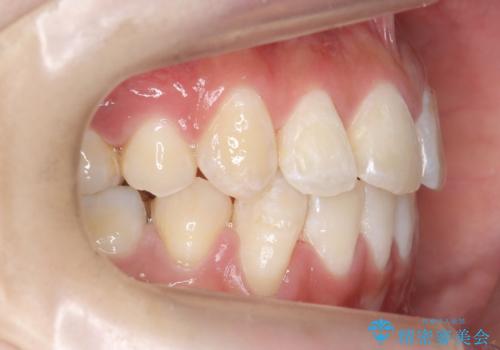

八重歯の治療 仕上がり重視で

- 八重歯を主訴に来院。

仕上がり重視とのことで、小臼歯を抜歯し、スタンダードな治療方法で仕上げています。

上下の小臼歯を抜歯しています。

矯正用インプラントアンカーを使用してしっかり前歯を下げたため、口元が大きく改善しています。